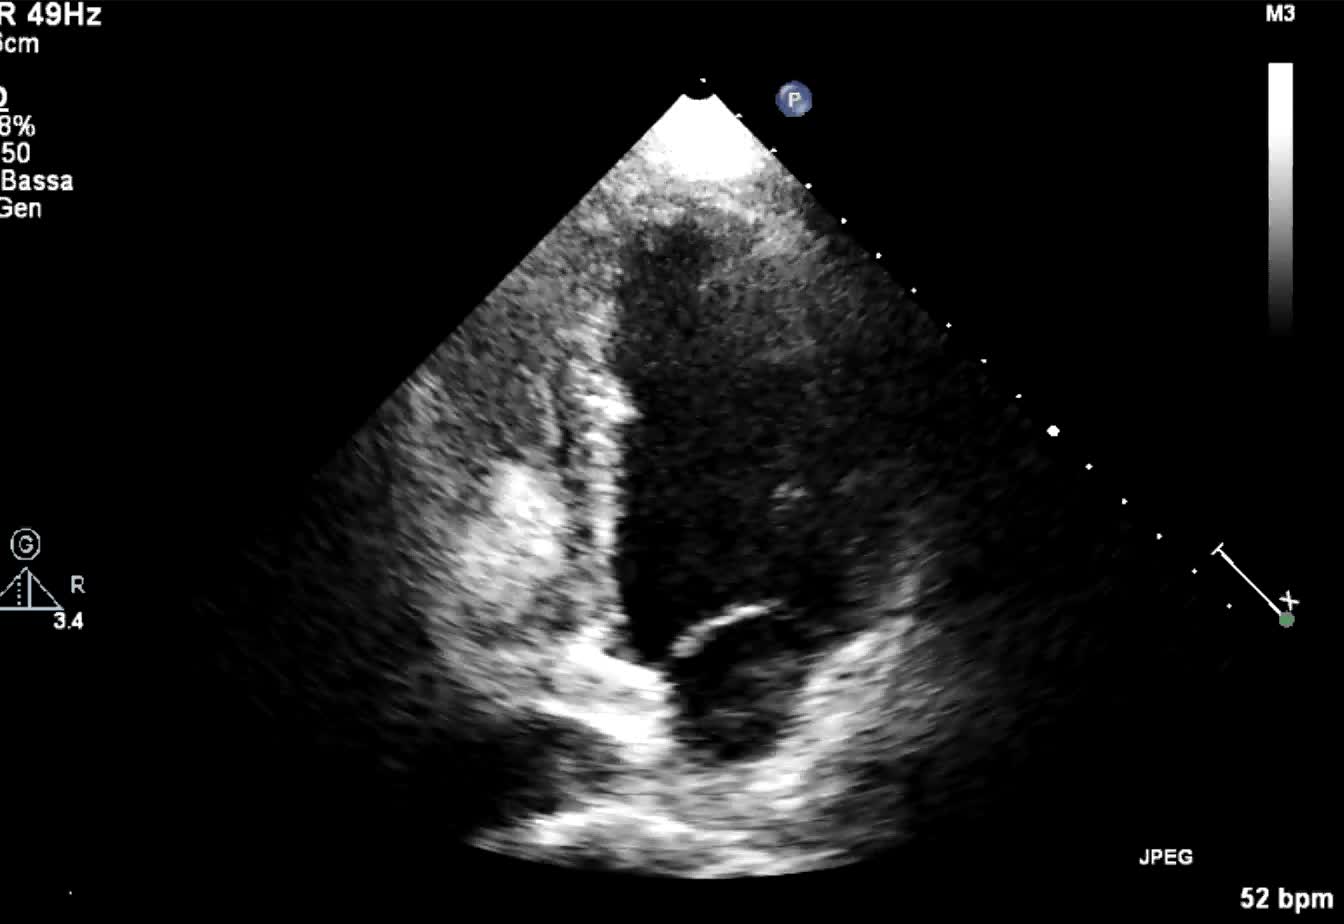

Titolo:

Metastasi cardiaca di carcinoma tiroideo

Autore:

Andrea Barbieri